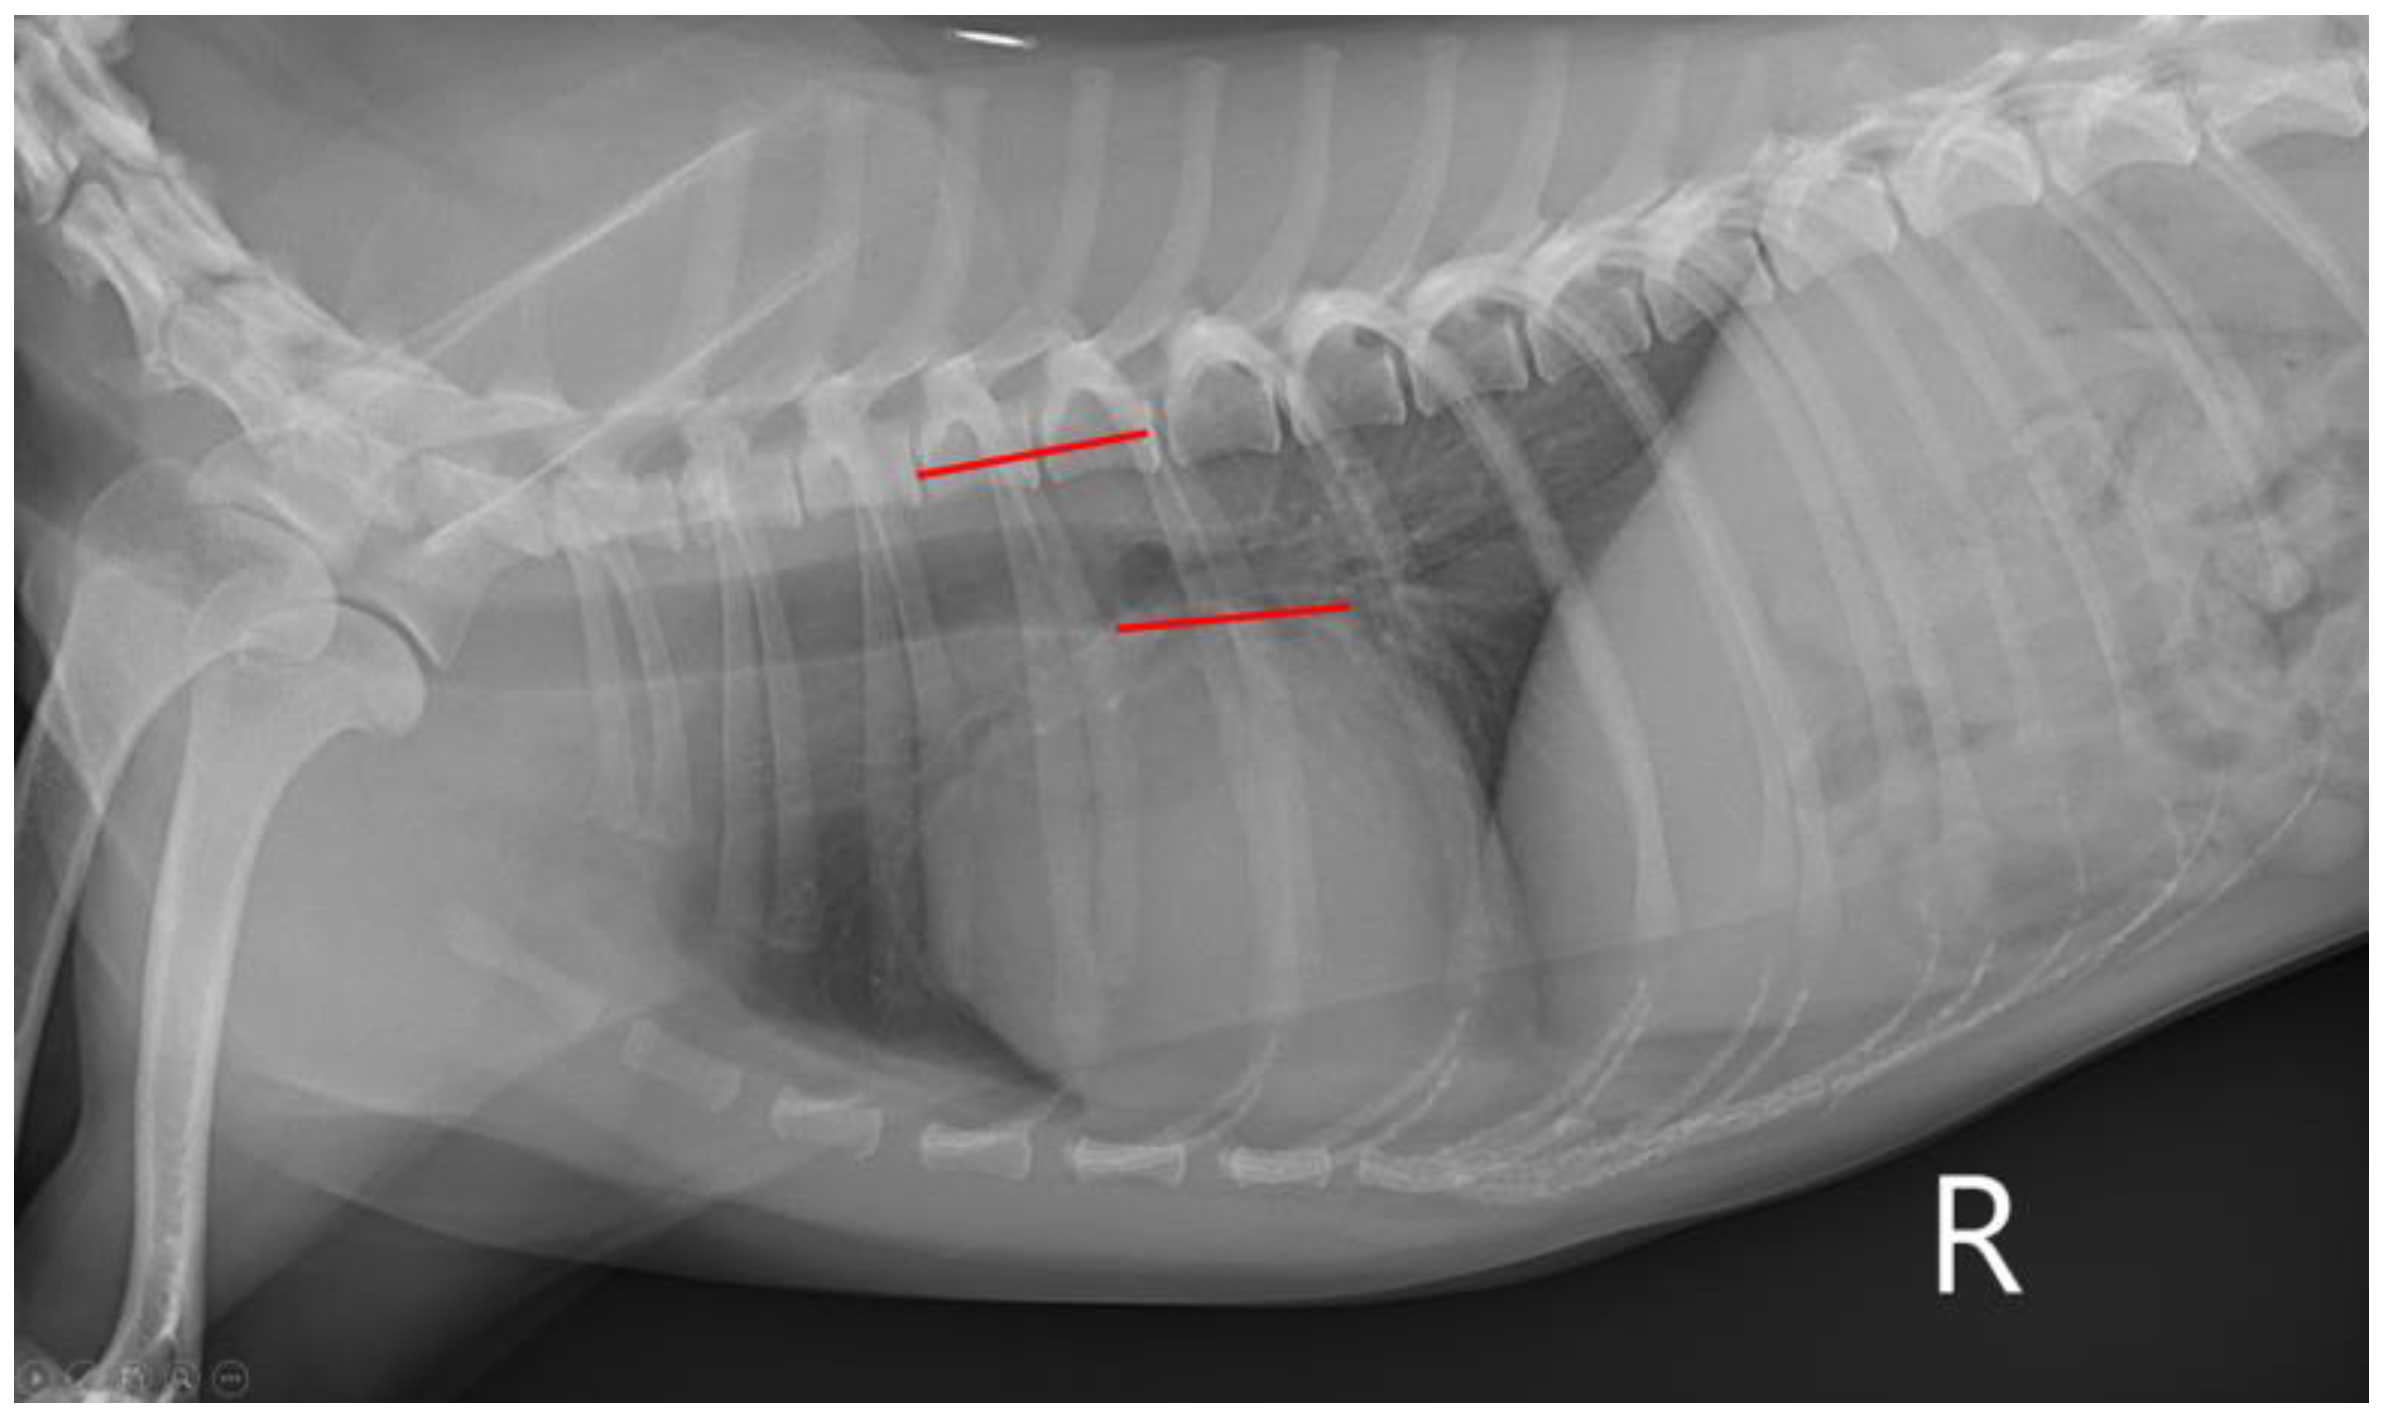

2.2. Thoracic Radiography

| VHS | 10.15 (9.60–10.50) | 10.50 (9.58–10.68) | 11.20 (10.80–12.00) | <0.001 | a,b < c α,γ,ε |

| VLAS | 1.40 (1.20–1.50) | 1.50 (1.40–1.60) | 1.90 (1.80–2.30) | <0.001 | a,b < c α,γ,ε |